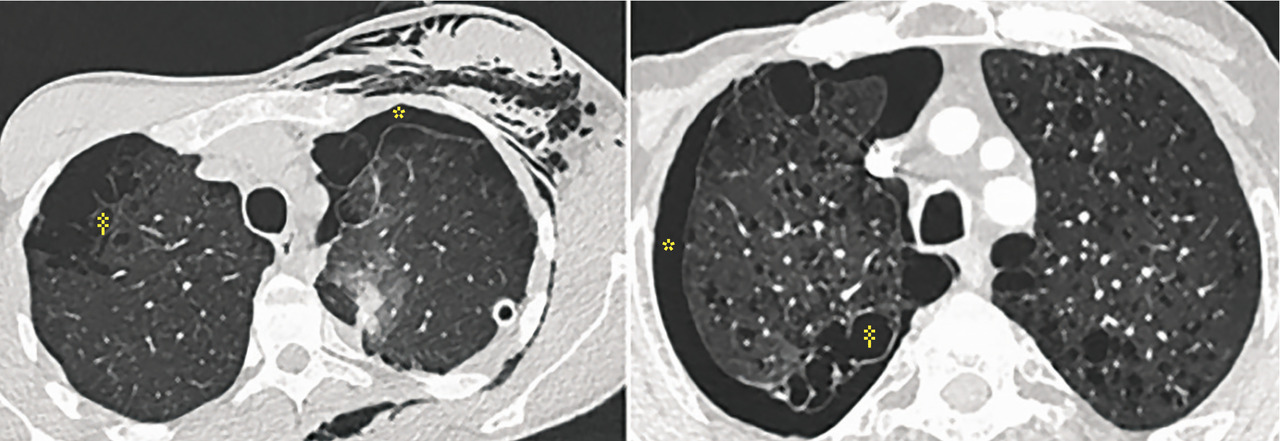

Parmi les patients d’une série française4 souffrant de pneumothorax spontané (n = 83), 85 % étaient fumeurs de tabac (n = 70) dont la moitié consommateurs de cannabis (n = 32), avec en moyenne un usage important de 30 JA (IC 25-75 : 10 à 31). Les scanners thoraciques ont montré un emphysème chez de nombreux sujets (50 % des consommateurs de tabac seul, 71 % des fumeurs tabac-cannabis). Dans ce dernier groupe, les malades étaient plus jeunes (35 ans vs 46 ans, p = 0,009) et consommaient moins de tabac en paquet-années (p = 0,02 ;figure ). Ainsi, fumer du cannabis, ajouté au tabac, majore le risque d’emphysème.

Parmi les patients d’une série française4 souffrant de pneumothorax spontané (n = 83), 85 % étaient fumeurs de tabac (n = 70) dont la moitié consommateurs de cannabis (n = 32), avec en moyenne un usage important de 30 JA (IC 25-75 : 10 à 31). Les scanners thoraciques ont montré un emphysème chez de nombreux sujets (50 % des consommateurs de tabac seul, 71 % des fumeurs tabac-cannabis). Dans ce dernier groupe, les malades étaient plus jeunes (35 ans vs 46 ans, p = 0,009) et consommaient moins de tabac en paquet-années (p = 0,02 ;